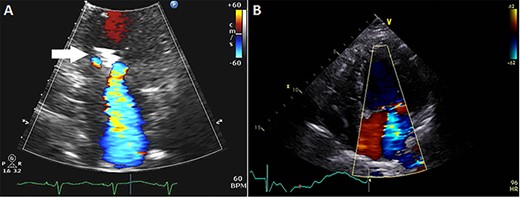

Subsequently, the patient was brought to our institution with progressive shortness of breath and altered mental status. She was noted to be hypotensive requiring intravenous fluid, vasopressors and was treated for pneumonia. During that hospitalization, the patient had an echocardiogram showing LVEF 30% and moderate–severe MR with a mitral clip visualized (Fig. 1A). The patient was further evaluated with a dobutamine study that showed slight improvement in the LVEF and a hyperdynamic right ventricle. The patient recovered from this hospitalization, but her functional status continued to decline. She had an echocardiogram 3 months after her hospitalization, which showed worsening LVEF of 15–20% and severe MR likely secondary to worsening LV dilatation exacerbated by her acute illness (Fig. 1B). Given the ongoing symptoms and worsening LV function, our multidisciplinary team recommended MV replacement in an effort to improve symptoms, reduce the incidence of hospitalizations and preserve the remaining LV function.

(A) Echocardiogram showing mitral clip (white arrow) at 4 months after clip placement; (B) at 7 months, left ventricular ejection fraction was 15–20%, diastolic and systolic diameters were 54 and 51 mm, respectively, and mean transmitral gradient 2.1 mmHg.